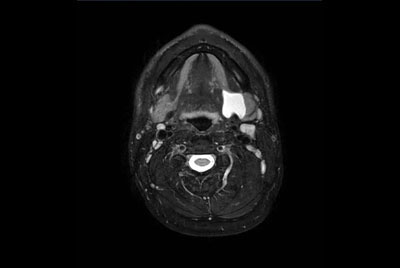

Soft Tissue of the neck